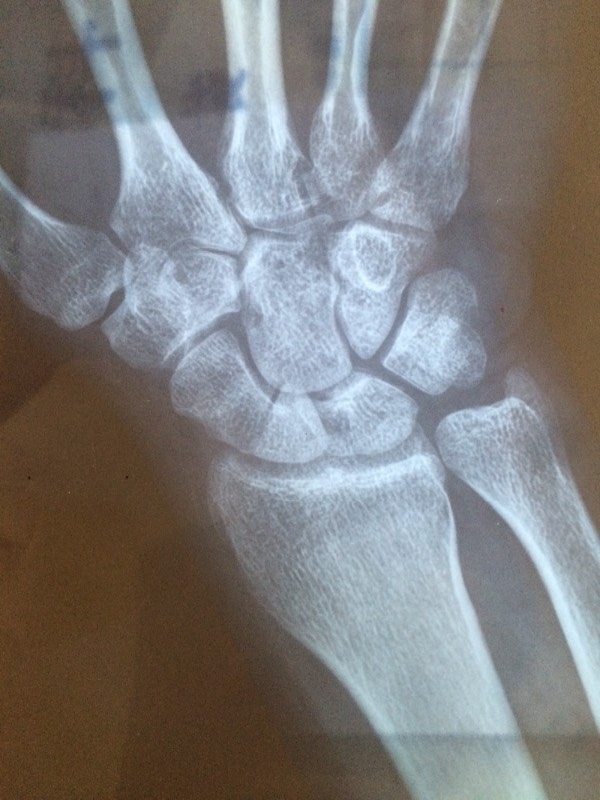

右手舟状骨断裂四十多天了,之后拍的照片,医生帮我看看涨了没有,我

关键词 手舟骨x片